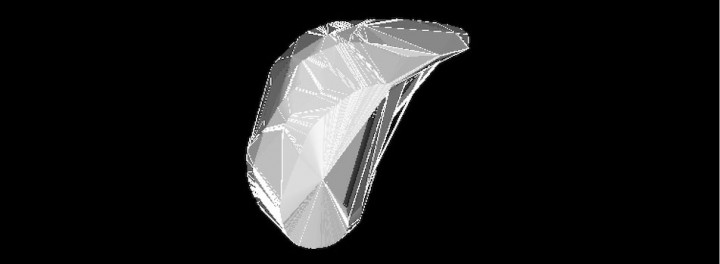

En el caso de que las masas cardiacas no sean extirpables, puede realizarse una medición del volumen de la masa y realizar comparaciones pre y posquimioterapia para evaluar la eficacia del tratamiento teniendo datos mucho más objetivos y precisos que las mediciones en imágenes en 2D. Estas técnicas de software llamadas volume rendering se aplican en medicina humana de manera rutinaria (Fig. 11).[ Uchiyima Y: Changes in the Submandibular Gland in Patients with Head and Neck Cancer After Radiation Therapy: A Preliminary Study. Anticancer Res 2017; 37(6):3239-3242. [PubMed] ]

<p>Reconstrucción volumétrica de neoplasia cardiaca mediante <em>volume rendering</em> que permite calcular el volumen de la masa.</p>

Reconstrucción volumétrica de neoplasia cardiaca mediante volume rendering que permite calcular el volumen de la masa.